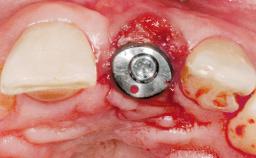

Immediate Flapless Placement of an Implant in a Maxillary Right Lateral Incisor Site

This 43-year-old male patient, a non-smoker, came to our practice because of a fracture of tooth 12 caused by a bicycle accident. Due to the combined para- and infrabony crown and root fracture, tooth extraction, and subsequent implant placement were suggested to the patient as the therapy of choice. The patient had high esthetic expectations with regard to the treatment outcome and asked for an immediate fixed provisional restoration. His individual esthetic risk profile summed up to a medium esthetic risk.

Abutment Type CAD/CAM

Prosthesis Type FDP

Loading Protocol Immediate

Retention Screw-retained Screw-retained

Provisional Implant-Supported Prosthesis Prosthodontic margin > 3 mm apical to mucosal margin Prosthodontic margin > 3 mm apical to mucosal margin